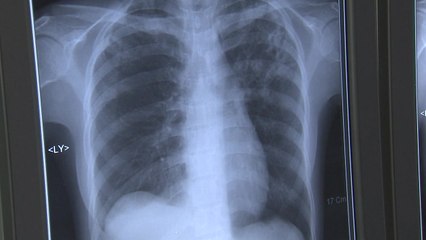

■ 진행 : 김영수 앵커, 강려원 앵커 br ■ 출연 : 류재복 해설위원 br br * 아래 텍스트는 실제 방송 내용과 차이가 있을 수 있으니 보다 정확한 내용은 방송으로 확인하시기 바랍니다. br br br 코로나19 발생은 나라 밖에서 들어오는 환자와 국내에서 확진 판정을 받는 환자로 나뉘는데요. 두 부류의 성격이 확연하게 다르기 때문에 분석 또 대응 방법도 차이가 있습니다. br br 최근 상황을 종합해 보면 국내 발생은 어느 정도 누그러지는 모습인데 해외 유입 환자는 많이 늘어나고 있습니다. 어떻게 해석해야 하고 또 어떤 처방이 필요한지 류재복 해설위원과 함께 알아보도록 하겠습니다. br br 어서 오세요. 오늘 코로나19 신규 환자 가운데 외국에서 유입된 환자가 크게 늘었어요. 거의 3분의 2에 해당하거든요. br br [류재복] br 그렇습니다. 62명이 새 환자인데요. 이 가운데 43명이 해외에서 들어왔습니다. 특히 오늘은 필리핀에서 들어온 사람 가운데 확진자가 16명이 나왔는데요. 이것은 선원 교체기입니다. br br 그러니까 우리나라에서 고기를 잡는 것과 농사 짓는 부분에서 외국인 노동자들이 많이 들어오는데 특히 선원을 어느 정도 일하고 나면 교체를 하는데 이 교체기 때 필리핀 사람들이 꽤 많이 들어온다고 하는데 거기서 확진 판정을 받은 게 특이한 부분입니다. br br 그리고 발생을 분석해 보면 아까 말씀하신 것처럼 전체적으로 하루 발생은 그렇게 크게 늘거나 줄거나 하지는 않은 것 같고요. 그런데 비수도권이 많이 늘었죠. br br 비수도권, 그러니까 5월부터 두 달 정도는 수도권을 중심으로 발생들이 있었는데 지난주를 보니까, 2주를 보니까 비수도권이 16.7명, 수도권이 15명. 이렇게 돼서 비수도권이 이제 더 많습니다. br br 대전충남, 광주전남 이 지역이 지금 계속 늘어나는 그런 상황이고요. 현재는 대전충남은 어느 정도 잦아든 것 같고 광주전남 쪽은 아직도 산발적인 발생이 있습니다. br br 그다음에 집단 감염은 19건에서 7건으로 12건이 줄었습니다. 그리고 깜깜이 환자라고 해서 원인을 알 수 없는 발병은 9.4니까 큰 차이가 없고요. 방역망 내 관리 비율은 여전히 80 미만입니다. br br br 사실 속도가 조금 느리기는 하지만 국내 발생은 조금씩, 조금씩 잦아드는 모습을 보이기는 하는데 아까 말씀하신 대로 외국에서 들어온 환자가 계속 늘어나고 있는 것 아닙니까? br br [류재복] br 그렇습니다. 보면 오늘 0시 기준으로 전체 확진 ... (중략)br br ▶ 기사 원문 : ▶ 제보 안내 : , 모바일앱, social@ytn.co.